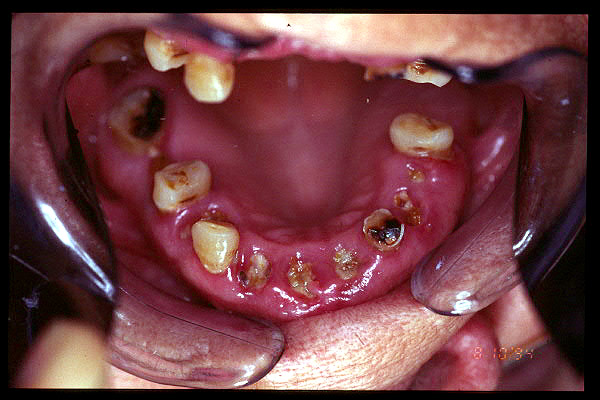

CM Edentulismo parcial, restos radiculares y caries